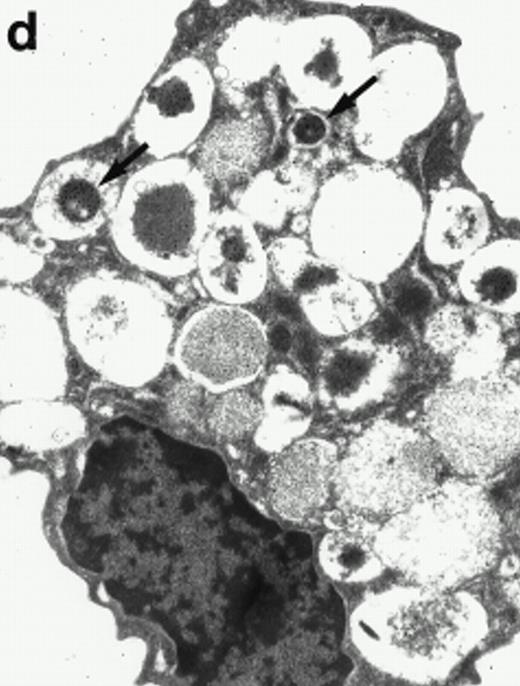

Morphologic analyses of both mature eosinophils and day-24 IL-5–induced UCC by immunoelectron microscopy were performed with proMBP-specific monoclonal antibody (J163-15E10) and with polyclonal antibody to MBP (rabbit #14). No proMBP staining was observed in peripheral blood eosinophils (Fig 6a); in contrast, MBP was localized specifically to the granule crystalline core (Fig 6b). Day-24 IL-5–induced UCC showed marked proMBP labeling of large uncondensed granules and minimal labeling of small condensed granules (Fig 6c); remarkably, proMBP was often seen as a ring around what appeared to be a granule in the process of condensing (black arrow). MBP labeling was confined primarily to condensing granules (Fig6d). Figure 7 shows results from double immunogold labeling of both proMBP (small gold) and MBP (large gold). ProMBP was concentrated in large uncondensed granules, and MBP was concentrated in condensed granules. Some granules (black arrow in Fig7b) contained labeling for MBP (primarily in the center) and proMBP (at the periphery). Controls using either normal mouse immunoglobulin or normal rabbit immunoglobulin as the primary label were negative (results not shown).

Localization of proMBP and MBP by immunoelectron microscopy. (a) A peripheral blood eosinophil labeled with anti-proMBP J163-15E10. Note the absence of specific labeling. (b) A peripheral blood eosinophil labeled with rabbit anti-MBP. Note that MBP is specifically localized to the granule crystalline core (black arrows). (c) Day-24 IL-5–induced UCC labeled with anti-proMBP. The black arrow shows localization of proMBP predominantly to the periphery of a condensing granule; very little proMBP is present in the interior of that granule. The white arrow points to a condensed granule, which lacks proMBP label. Also, note the presence of a large uncondensed granule densely labeled with proMBP proximal to the nucleus (open white arrowhead). (d) Day-24 IL-5–induced UCC labeled with anti-MBP. MBP is localized primarily to the interior of condensing granules (black arrows). (a, c, and d) Original magnification ×11,000; (b) ×15,000.